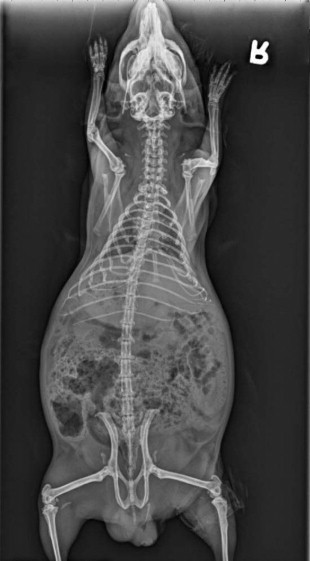

Whole body radiographs may provide a large amount of information for the veterinarian treating an ill patient. Both lateral and ventrodorsal (or dorsoventral) views should be obtained (Figure 17-9, Figure 17-10 ). To minimize rotation, care should be taken to extend the limbs symmetrically when positioning the patient. Because guinea pigs have stocky builds with short limbs, and because they resent aggressive restraint, sedation or anesthesia is helpful in obtaining diagnostic radiographs as well as in reducing the patient's stress (Figure 17-11 ). Table 17-1 is a guideline for radiographic techniques used in common small mammal radiographic studies.

Figure 17-9.

Right lateral radiograph of a guinea pig. Note the moderate overgrowth of the apices of the mandibular molars and premolars, remodeling of ribs, and large amount of ingesta within the GI tract.

(Courtesy University of California–Davis.)

Figure 17-10.

Ventrodorsal radiograph of the same guinea pig pictured in Figure 17-9.